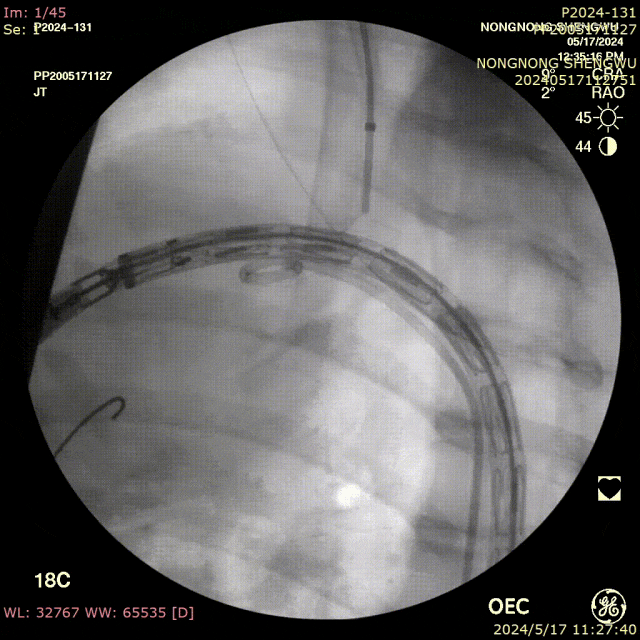

我们在两头35kg巴马公猪中完成动物实验:

成功实现弓上分支的快速、准确原位开窗;

破膜过程流畅,无分支或主动脉损伤;

取出标本可见圆形破口、支架贴合良好,证实技术可行性。

动物实验

巴马公猪35kg